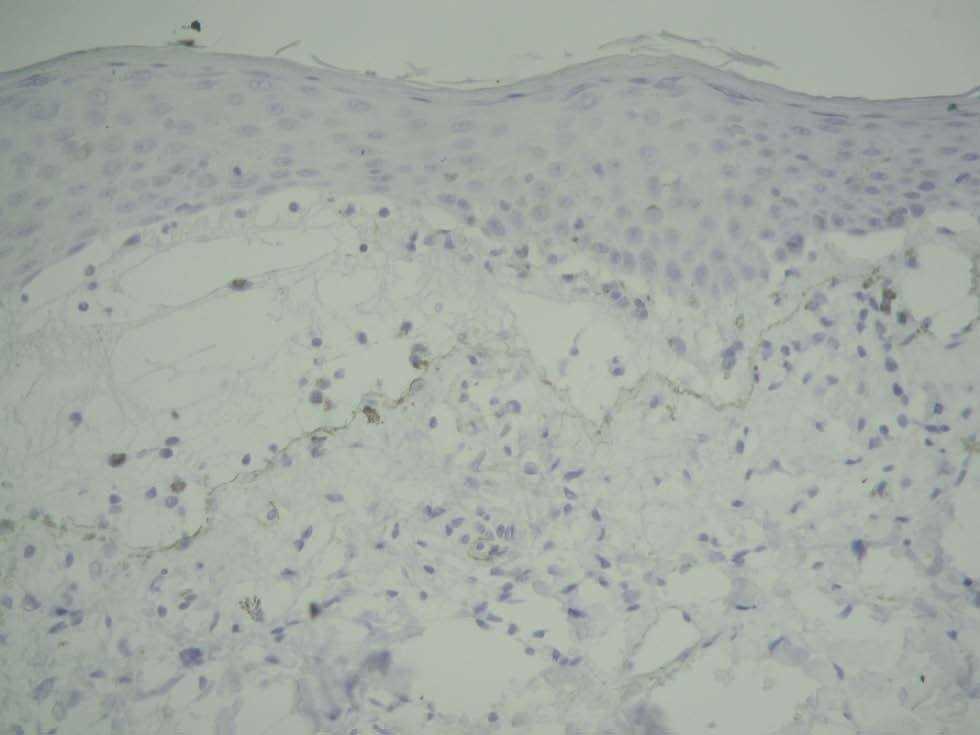

La biopsia del borde de una ampolla tensa mostró una imagen característica de penfigoide ampolloso (fig. 5). Se veía la formación de una ampolla subepidérmica con un infiltrado compuesto por linfocitos y eosinófilos. No existían cambios liquenoides en la epidermis sobre la ampolla. El estudio mediante inmunofluorescencia directa del área perilesional de la ampolla reveló un depósito lineal de C3 (fig. 6) y no se detectaron depósitos de IgG, IgM ni IgA. Mediante inmunohistoquímica se tiñó el colágeno IV (situado en la lámina densa de la membrana basal), y se vio que la separación se encontraba por encima del colágeno IV (fig. 7).

Fig. 7.—Inmunohistoquímica. Tinción del colágeno IV de la membrana basal (color pardo). Se aprecia que la separación patológica se produce por encima del colágeno IV.